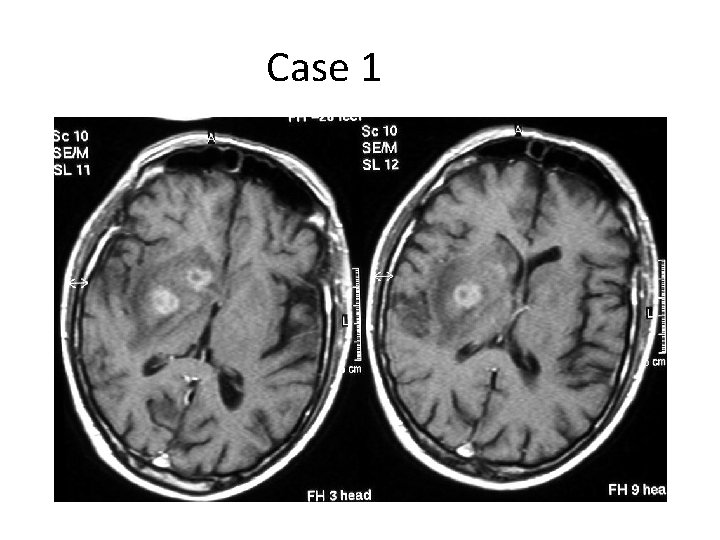

Case 1 • 65 M, HIV positive • HPI – Involuntary flinging mvmnts of Rt arm/leg – Worsened over 1 mo – Difficult to walk and use hand • O/E – Continuous wild, uncontrollable flapping and circular movements of Rt arm – Jerky mvments of Rt leg – Unsteady gait, falling to right

Case 1 • What would you call this movement disorder? • On the basis of the symptoms and signs, where is the lesion? • What is the most likely diagnosis and what are some possibilities?

Case 1 • Decreased inhibition of contralateral thalamus – Subthalamic lesion – Damage to indirect pathway